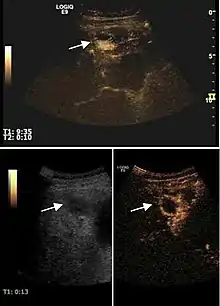

Liver abscess

Liver abscess have heteromorphic ultrasound appearance, the most typical being that of a mass with irregular shapes, fringed, with fluid or semifluid content, with or without air inside. Doppler examination shows the lack of vessels within the lesion. CEUS exploration shows hyperenhancement during arterial phase close to the lesion, this being suggestive of a liver parenchymal hyperemia. During venous and sinusoidal phase the pattern is hypoechoic, and the central fluid is contrast enhanced. CEUS examination is useful because it confirms the clinical suspicion of abscess. In addition, it allows for an accurate measurement of the collection size and an indication regarding its topography inside the liver (lobe, segment).